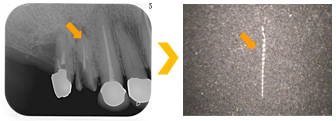

根管内に残っていた破折した金属リーマー。顕微鏡による的確に除去できた症例。

根管内に残っていた破折した金属リーマー。顕微鏡による的確に除去できた症例。

矢印の先に金属片状の不透過象が認められる。根尖に感染炎症による透過像を認める。

矢印の先に金属片状の不透過象が認められる。根尖に感染炎症による透過像を認める。

根管内の感染源と共に除去された。

根管内の感染源と共に除去された。